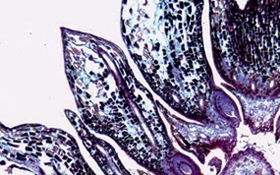

Nụ vị giác